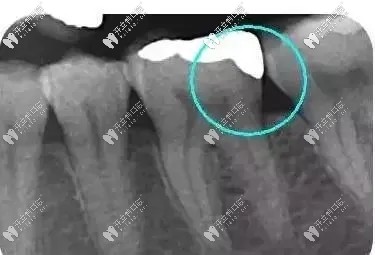

從下面這張X線中可以看出,嵌體遠(yuǎn)中邊緣沒有懸突,與牙體邊緣密合相接。

牙齒嵌體拍片圖示